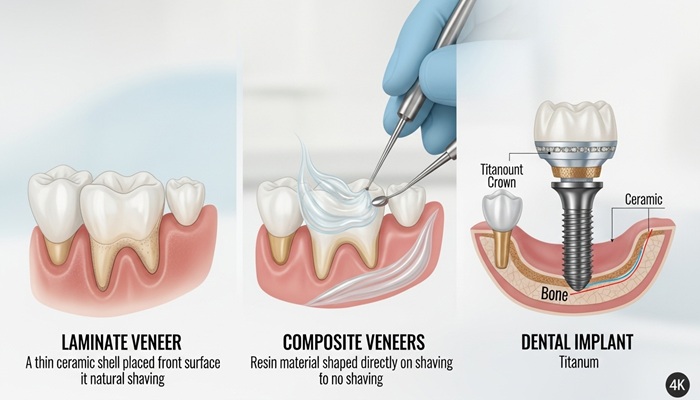

مورد اول اینکه پایه و تاج که از اجزای ایمپلنت دندان هستند از مواد با کیفیت و مستحکم ساخته می شود. بدین صورت که پایه ایمپلنت از جنس تیتانیوم و تاج دندان از جنس سرامیک است. از این رو ضمن داشتن استحکام و مقاومت بالا، به نسبت دوام و طول عمر ایمپلنت نیز افزایش می یابد. مورد دوم نیز مربوط به نحوه کاشت این نوع از دندان مصنوعی است.

A dental implant is an artificial tooth and root system. It consists of an implant root, an abutment, and a crown. The implant root is a titanium post with threads (ridges) like a screw. The implant root is surgically placed in the jaw bone. Titanium is a biocompatible material that will fuse with the bone through a process called osseointegration. This process takes a few months, but once a solid bond is formed, it can last for many years.

ایمپلنت دندان یک سیستم دندان و ریشه مصنوعی است. از یک ریشه ایمپلنت، یک اباتمنت و یک تاج تشکیل شده است. ریشه ایمپلنت یک پست تیتانیومی با رزوه ها (برآمدگی ها) مانند پیچ است. ریشه ایمپلنت با جراحی در استخوان فک قرار می گیرد. تیتانیوم یک ماده زیست سازگار است که از طریق فرآیندی به نام osseointegration با استخوان ترکیب می شود. این فرآیند چند ماه طول می کشد، اما هنگامی که یک پیوند محکم تشکیل می شود، می تواند سال ها ادامه یابد.

با توجه به اینکه فیکچسر ایمپلنت دندان درون استخوان فک کاشته می شود؛ به دلیل پیوند استخوان فک با پایه تیتانیومی، استحکام ایمپلنت به طور قابل توجهی افزایش خواهد یافت. تا جایی که از ایمپلنت های کاشته شده، می توان مثل دندان های طبیعی استفاده کرد. با این توصیف می توان گفت کیفیت اجزای سازنده ایمپلنت تأثیر بسزایی در دوام و طول عمر ایمپلنت دندان دارد. اگر هنوز بین انجام ایمپلنت یا روکش دندانی تردید دارید مقاله ایمپلنت بهتر است یا روکش را از دست ندهید.